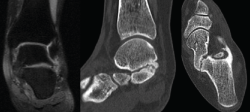

Se trata de una de las causas más comunes del pie plano rígido doloroso en la población pediátrica(9,10,11). El dolor es el síntoma predominante(12,13,14) y de consulta, especialmente tras la actividad física. Los esguinces de repetición, desaxaciones, pies planos y contracturas de peroneos son también formas de presentación habituales (Figura 2). Llegaremos al diagnóstico de dicha patología por sospecha clínica y radiológica, y confirmación por tomografía axial computarizada (TAC) y eventualmente resonancia magnética nuclear (RMN)(15)(Figura 3).

Figura 3. Confirmación de la coalición por resonancia magnética nuclear y tomografía axial computarizada.